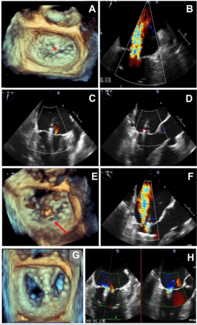

An 80-year-old man was referred to our center for heart failure and severe degenerative mitral regurgitation (MR). Transesophageal echocardiography revealed severe MR due to anterior leaflet prolapse, mainly in its central portion (A2) in the...